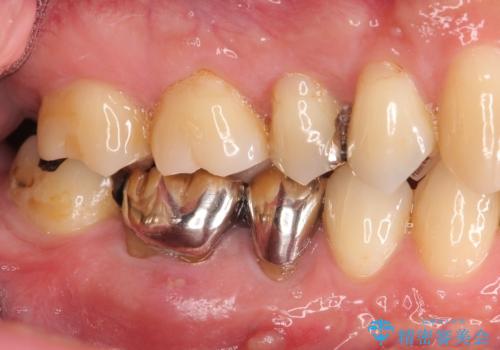

- 食事のたびに、銀歯の間や周囲に食ベカスが挟まったり溜まったりすることの改善を求めて来院されました。

銀歯の形状に問題があり、食べかすの詰まりやすい状況を、精度の高いセラミッククラウンに置き替えることで不快症状の改善を計画します。